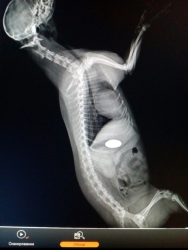

Специалисты саратовской ветлечебницы №1 спасли пса, проглотившего пуговицу. Как сообщает управление ветеринарии правительства Саратовской области, помощь потребовалась йоркширскому терьеру Жуже.

"Животное отказывалось от пищи, было вялым. Ветеринарные специалисты с помощью рентгена определили, что собака проглотила пуговицу, и она находится в желудке", - сообщают ветеринары.

Двухсантиметровую пуговицу из терьера достали, сейчас Жужа успешно проходит восстановительный период.